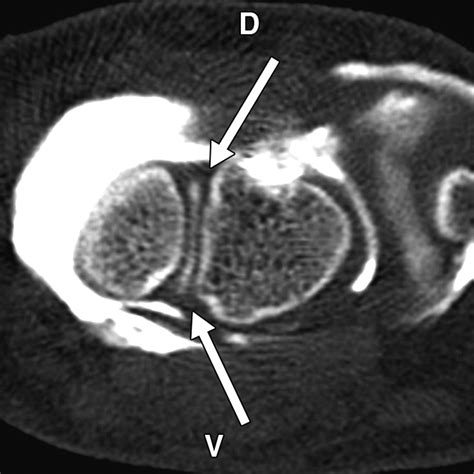

Diagnosing this condition requires a comprehensive physical examination combined with advanced imaging. Physicians typically rely on standard X-rays, which often reveal the characteristic gap in the scaphoid and the narrowing of the joint space. In more complex cases, a CT scan or MRI may be ordered to assess the exact degree of cartilage degradation and to plan potential surgical interventions.

• scaphoid nonunion advanced collapse radiology